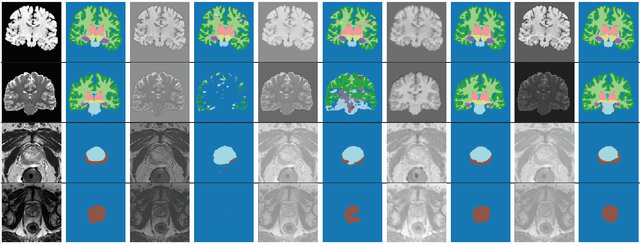

Abstract:Performance of convolutional neural networks (CNNs) in image analysis tasks is often marred in the presence of acquisition-related distribution shifts between training and test images. Recently, it has been proposed to tackle this problem by fine-tuning trained CNNs for each test image. Such test-time-adaptation (TTA) is a promising and practical strategy for improving robustness to distribution shifts as it requires neither data sharing between institutions nor annotating additional data. Previous TTA methods use a helper model to increase similarity between outputs and/or features extracted from a test image with those of the training images. Such helpers, which are typically modeled using CNNs, can be task-specific and themselves vulnerable to distribution shifts in their inputs. To overcome these problems, we propose to carry out TTA by matching the feature distributions of test and training images, as modelled by a field-of-experts (FoE) prior. FoEs model complicated probability distributions as products of many simpler expert distributions. We use 1D marginal distributions of a trained task CNN's features as experts in the FoE model. Further, we compute principal components of patches of the task CNN's features, and consider the distributions of PCA loadings as additional experts. We validate the method on 5 MRI segmentation tasks (healthy tissues in 4 anatomical regions and lesions in 1 one anatomy), using data from 17 clinics, and on a MRI registration task, using data from 3 clinics. We find that the proposed FoE-based TTA is generically applicable in multiple tasks, and outperforms all previous TTA methods for lesion segmentation. For healthy tissue segmentation, the proposed method outperforms other task-agnostic methods, but a previous TTA method which is specifically designed for segmentation performs the best for most of the tested datasets. Our code is publicly available.